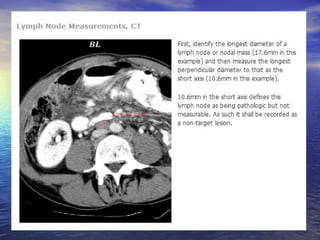

Avaliação dos linfonodos:

Linfonodos: eixo curto ≥ 15mm: lesão mensurável (target lesion);

Linfonodos: eixo curto < 10mm: “não patológicos”;

Linfonodos: eixo curto ≥ 10mm e < 15mm: nontarget lesions;